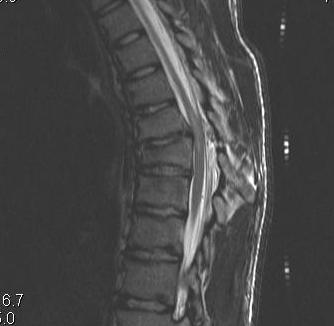

MRI

- HNP

- cord signal change

- assess posterior ligament integrity

- assess level of conus medullaris